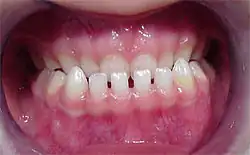

Diastemas em dentes inferiores.

Diastema é uma lacuna ou espaço entre dois dentes. O termo é mais comumente aplicado a um espaço aberto entre os incisivos superiores (dentes frontais). Ela acontece quando há uma relação desigual entre o tamanho dos dentes e da maxila. Muitas espécies de mamíferos têm diastema como uma característica normal.[1][2][3]